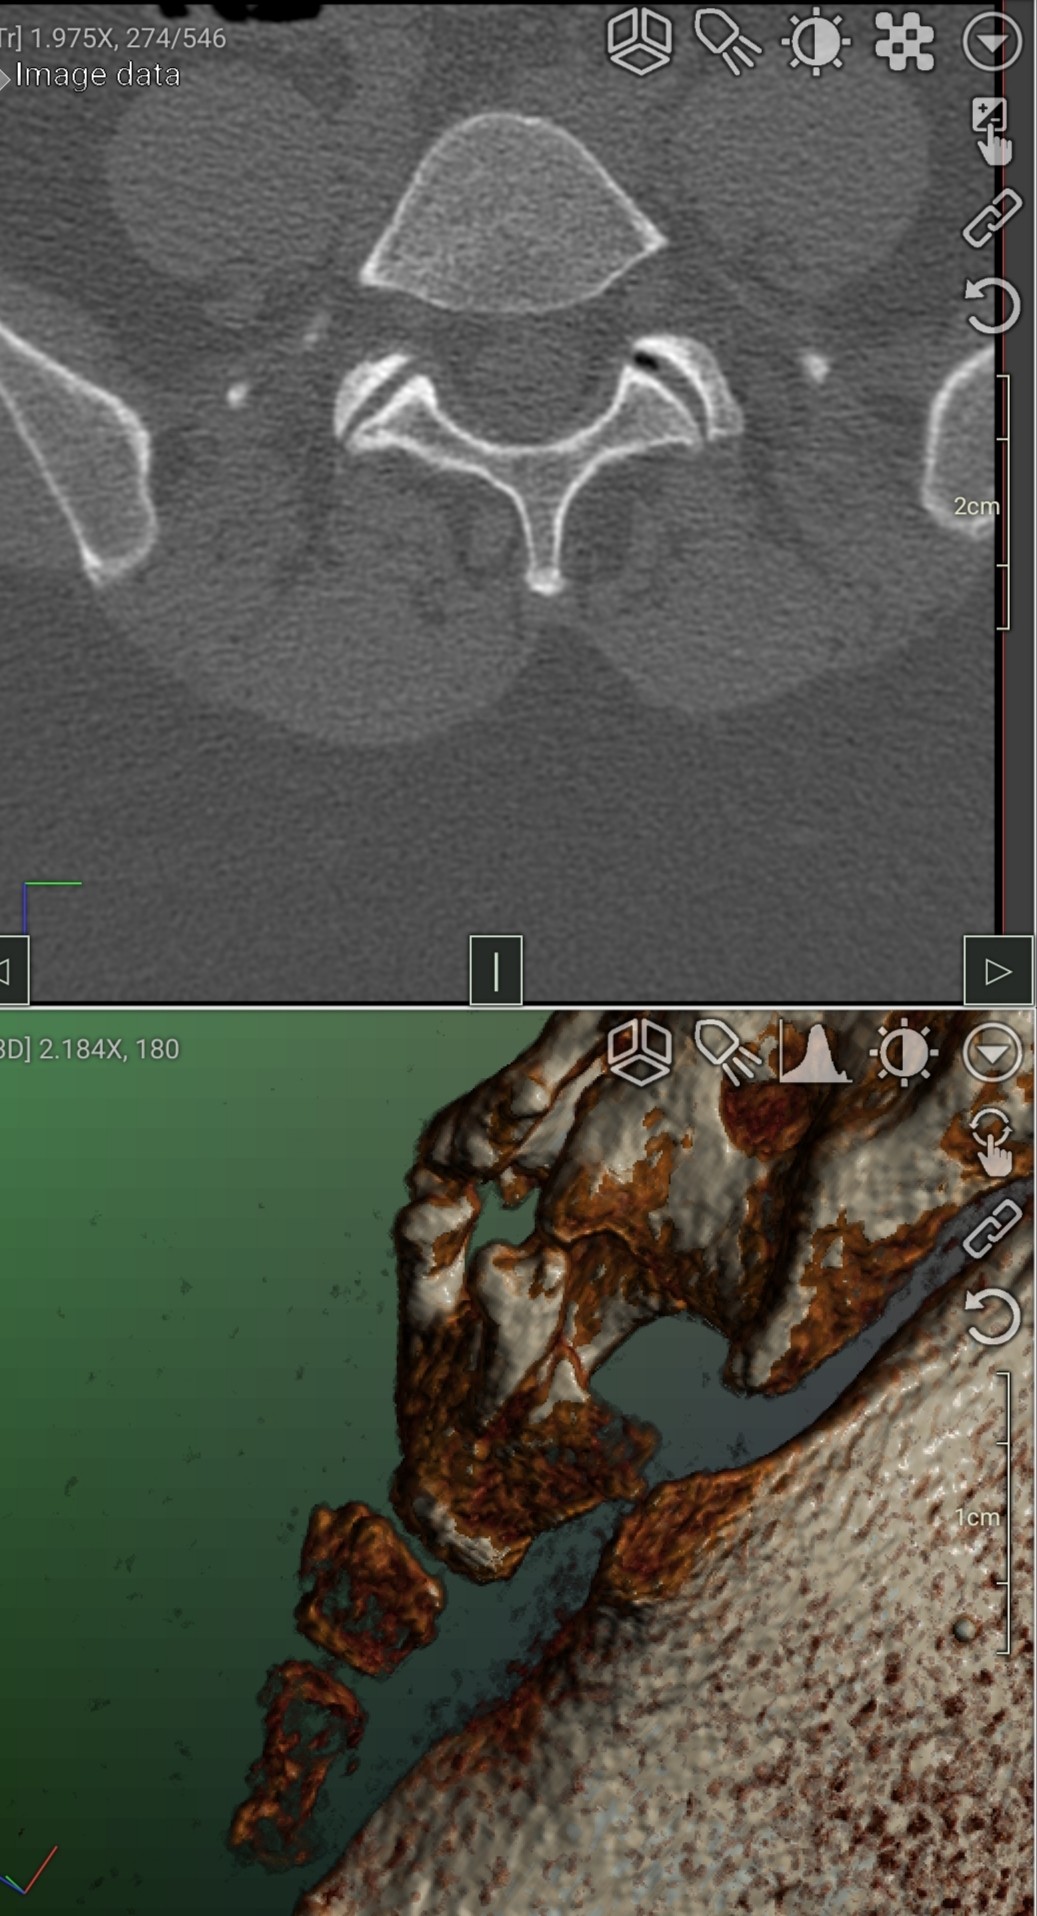

Здравствуйте, подскажите, пожалуйста. Неделю назад подскользнулась на лестнице и получила травму в районе копчика. Сделали КТ, жду результат. Проконсультируйте, почему болит? Есть ли ушиб или вывих? Болит при наклоне, вставании, при напряжении в районе ануса, при лежании на спине. Когда хожу чувствую распирание и напряжение в районе копчика, но не болит. Заранее благодарю.